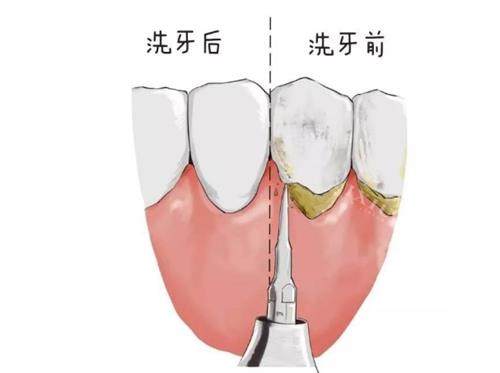

四、洗牙与牙周治疗价格参考

超声波洁牙(工作日):90 元起(含基础检查)

超声波洁牙(节假日):110 元起(含基础检查)

喷砂 + 抛光 + 洁牙套餐:160 元起(含牙周上药)

牙周龈下刮治(单象限):420 元起

牙周袋冲洗(单次):80 元起